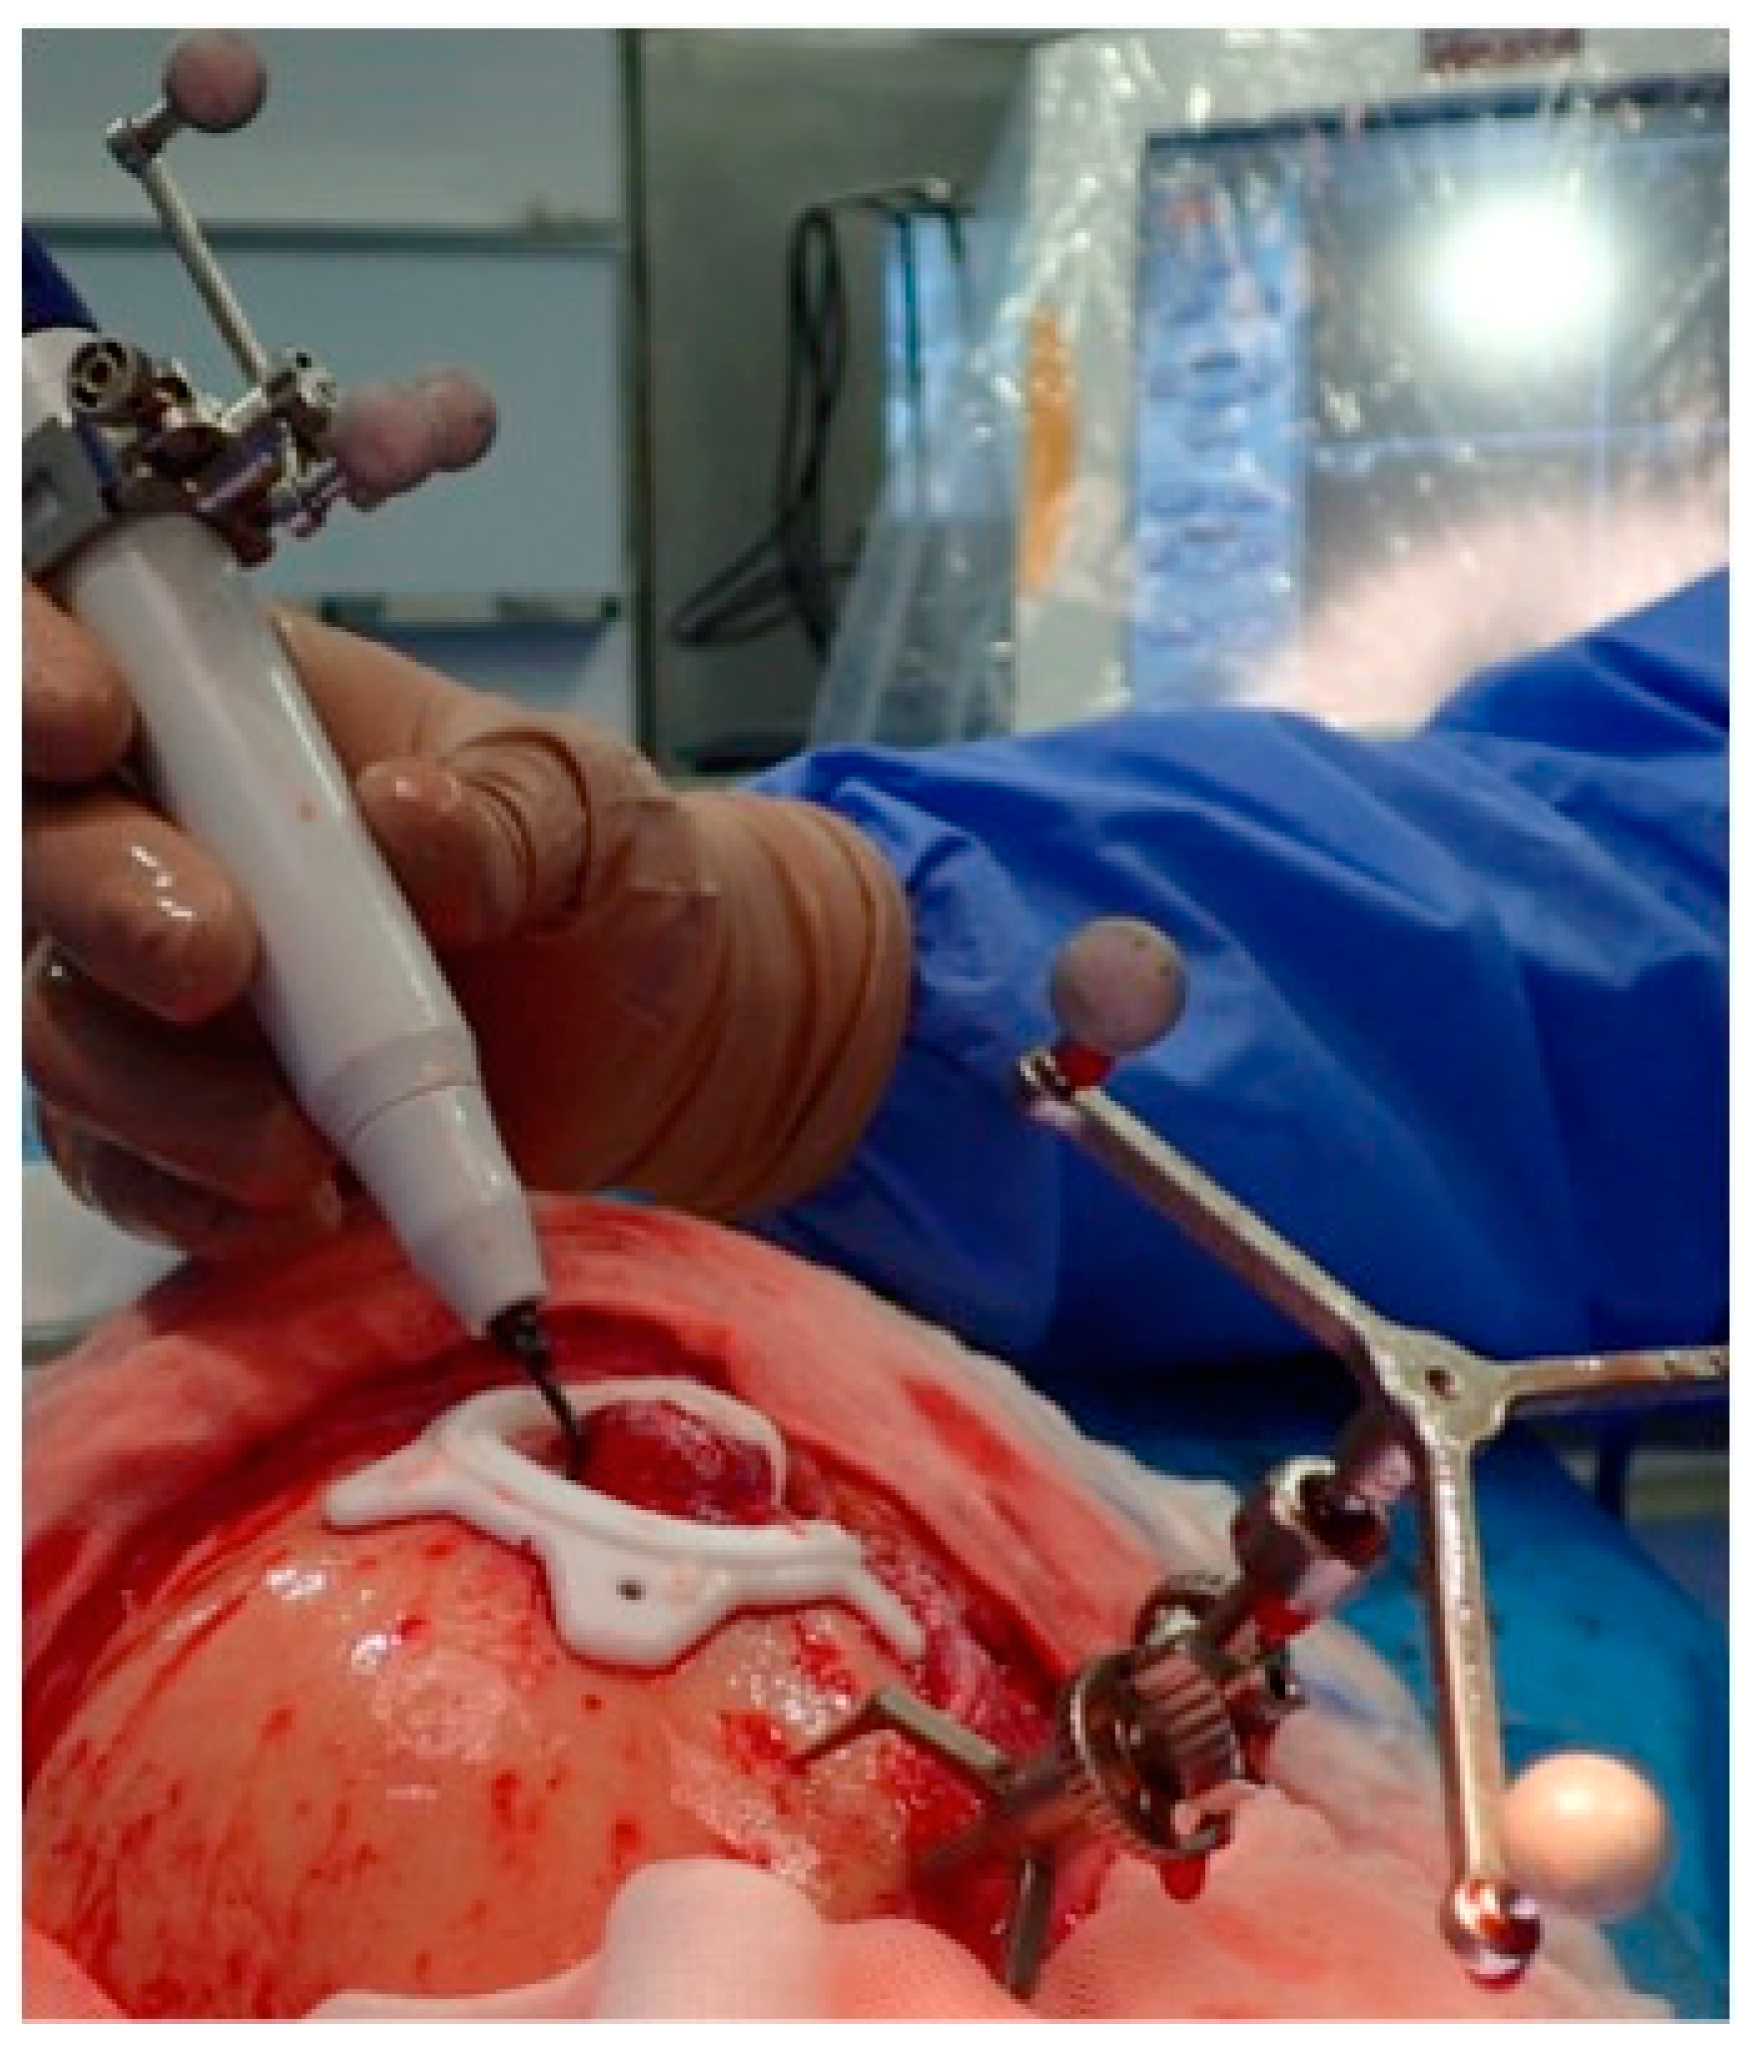

2.3.3. Surgical Navigation

| 1 | 53/F | L/25 mm | Y | 4 mo | Dystopia | N | CT, MRI | Supraorbital rim, orbital roof | Intraosseous venous malformation | - | Resection + reconstruction | Y | Y | 1st, 2nd, 3rd | Coronal | Y | Piezoelectric device | N | PEEK prosthesis | 7 y/N |

| 2 | 54/F | R/33 mm | Y | 9 y | N | Y | CT, MRI | Frontal bone, orbital roof | Intraosseous venous malformation | - | Resection + reconstruction | Y | Y | 1st, 2nd, 3rd | Coronal | Y | Piezoelectric device | N | PEEK prosthesis | 6 y/N |

| 3 | 36/F | L/19 mm | Y | 6 mo | N | N | CT, MRI | Zygoma | Arteriovenous malformation | - | Resection + reconstruction | Y | Y | 1st, 2nd, 3rd | Transconjunctival + blepharoplasty + maxillary vestibular | Y | Piezoelectric device | N | PEEK prosthesis | 5 y/N |

| 4 | 47/M | L/30 mm | N | 2 y | N | N | CT | Zygoma | Intraosseous venous malformation | - | Resection + reconstruction | Y | Y | 1st, 2nd, 3rd | Transconjunctival + lateral canthotomy + maxillary vestibular | Y | Piezoelectric device | N | PEEK prosthesis | 6 y/N |